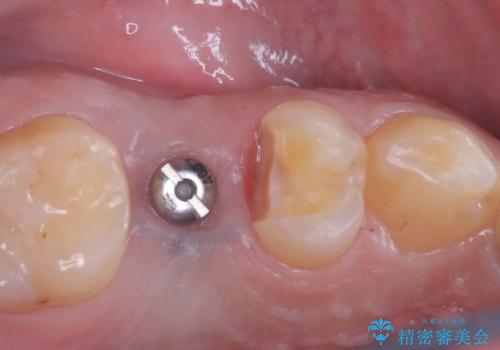

- 「歯茎にニキビみたいのが出来て歯が揺れている」を主訴に来院された患者様です。

右上5番が根尖性歯周炎と歯周病が同時に併発しており、骨が大きく溶け、歯の動揺も著しかったため保存困難と判断をし抜歯してインプラントで治療を行いました。

インプラントはインプラント周囲炎になりにくいスクリュータイプを使用しています。